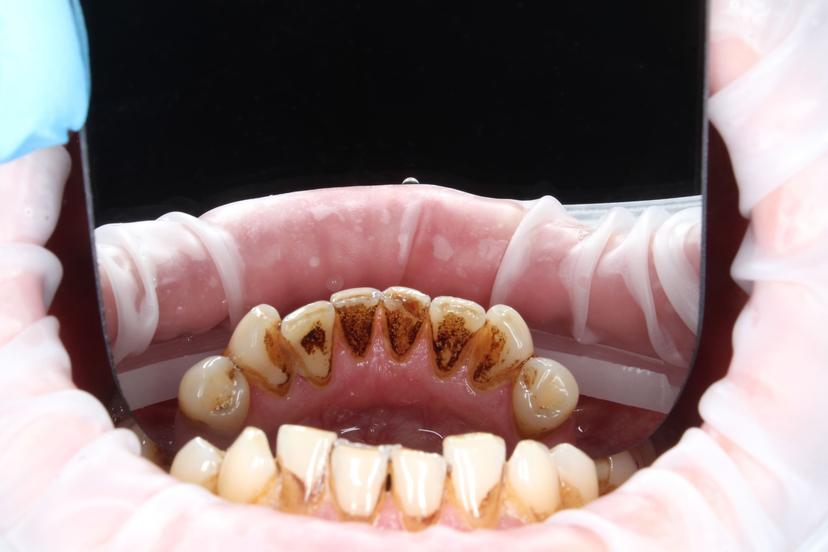

Пациент пришел с жалобами на неприятный запах изо рта и на темный налёт, который не убирается зубной щеткой.

Для снятия зубных отложений мы провели комплексную профилактическую гигиену с применениям ультразвука, AIR FLOW, щетки с пастой.